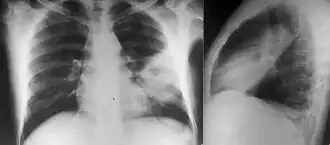

Various imaging modalities can also help with the diagnosis of melioidosis. In acute melioidosis with the spreading of the bacteria through the bloodstream, the chest X-ray shows multifocal nodular lesions. It may also show merging nodules or cavitations. For those with acute melioidosis without the spread to the bloodstream, chest x-ray most commonly shows upper lobe consolidation or cavitations.[9] In chronic melioidosis, the slowly progressing of upper lobe consolidation of the lungs resembles tuberculosis.[9] For abscesses located in other parts of the body apart from the lungs, especially in the liver and spleen, CT scan has higher sensitivity when compared with an ultrasound scan. In liver and splenic abscesses, an ultrasound scan shows "target-like" lesions while CT scan shows "honeycomb sign" (abscess with loculations separated by thin septa) in liver abscesses.[9] For melioidosis involving the brain, MRI have higher sensitivity than a CT scan in diagnosing the lesion. MRI shows ring-enhancing lesions for brain melioidosis.[9]

Diabetes mellitus is one of the most important risk factors in developing melioidosis. The disease should be considered in anyone who has spent time in endemic areas who develops a fever, pneumonia, or abscesses in their liver, spleen, prostate, or parotid gland.[1] The clinical manifestation of the disease can range from simple skin changes such as abscesses or ulcerations to severe organ problems.[7] The commonest organs affected are liver, spleen, lungs, prostate, and kidneys. Among the most common features are bacteremia (in 40 to 60% of cases), pneumonia (50%), and septic shock (20%).[1][8] People with only pneumonia may have a prominent cough with sputum and shortness of breath. However, those with septic shock together with pneumonia may have minimal coughing.[3] Results of a chest X-ray can range from diffuse nodular infiltrates in those with septic shock to progressive consolidation located most commonly in the upper lobes for those with pneumonia only. Pleural effusion and empyema are more common for melioidosis affecting lower lobes of the lungs.[3] In 10% of cases, people develop secondary pneumonia caused by other bacteria after the primary infection.[2] In northern Australia, 60% of the infected children presented with only skin lesions, while 20% presented with pneumonia.[2]